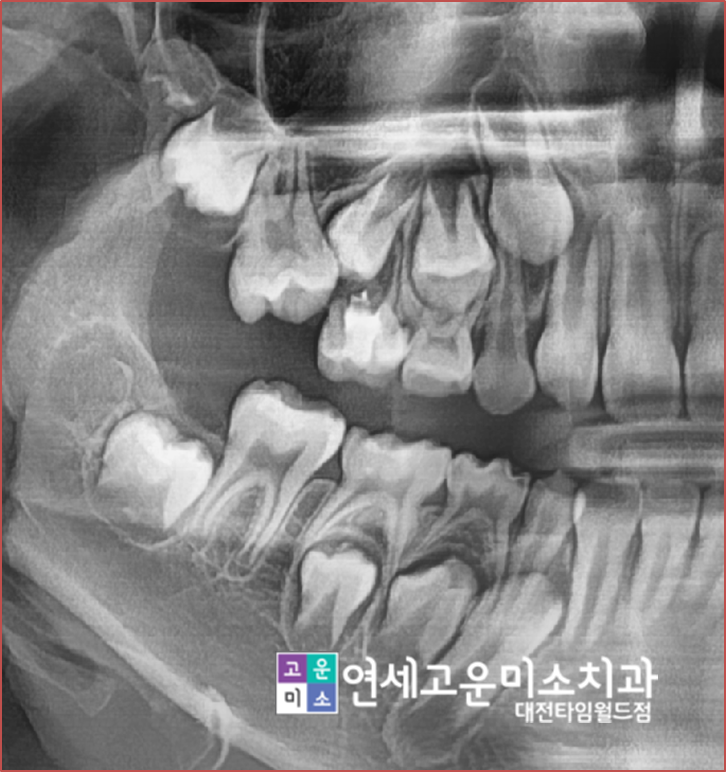

치아가 상실되고 나고 시간이 오래 지나면

위에 엑스레이처럼 옆에 치아가 그 공간으로 쓰러지게 됩니다.

저 상태에서는 임플란트를 할 수 없기 때문에

교정을 하지 않는다면

쓰러진 치아를 신경치료를 하고 씌운 뒤

임플란트를 하게 됩니다.

-->하지만 이렇게 치료를 하면

건전한 치아를 삭제해야 하는 단점이 생기고

쓰러진 채로 임플란트를 하기 때문에

음식물도 잘 낍니다.